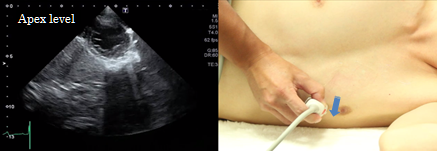

Apex level

At the apex level of the short axis view of the left ventricle, the image of the left ventricle should form a perfect circle. This view is used for evaluation of wall motion abnormalities. Since lesions confined to the apex can easily be missed, confirm the screen until the left ventricular cavity becomes invisible on the scanned image.